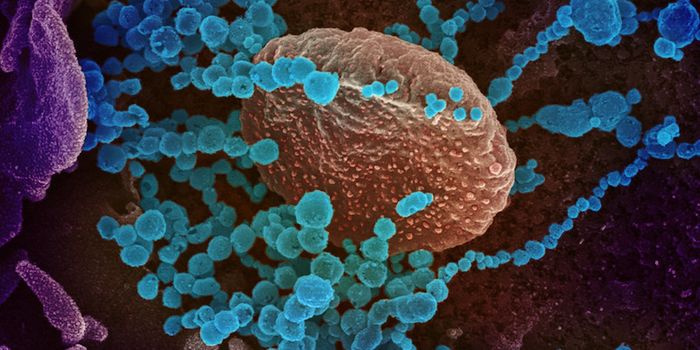

MAY 03, 2020Genetics & GenomicsThe origin of SARS-CoV-2, the pandemic virus that causes COVID-19, has become politicized as leaders seek to place blame ...

MAR 18, 2020MicrobiologySARS-CoV-2 is a coronavirus that causes an illness called COVID-19. There are now well over 210,000 confirmed cases worl ...